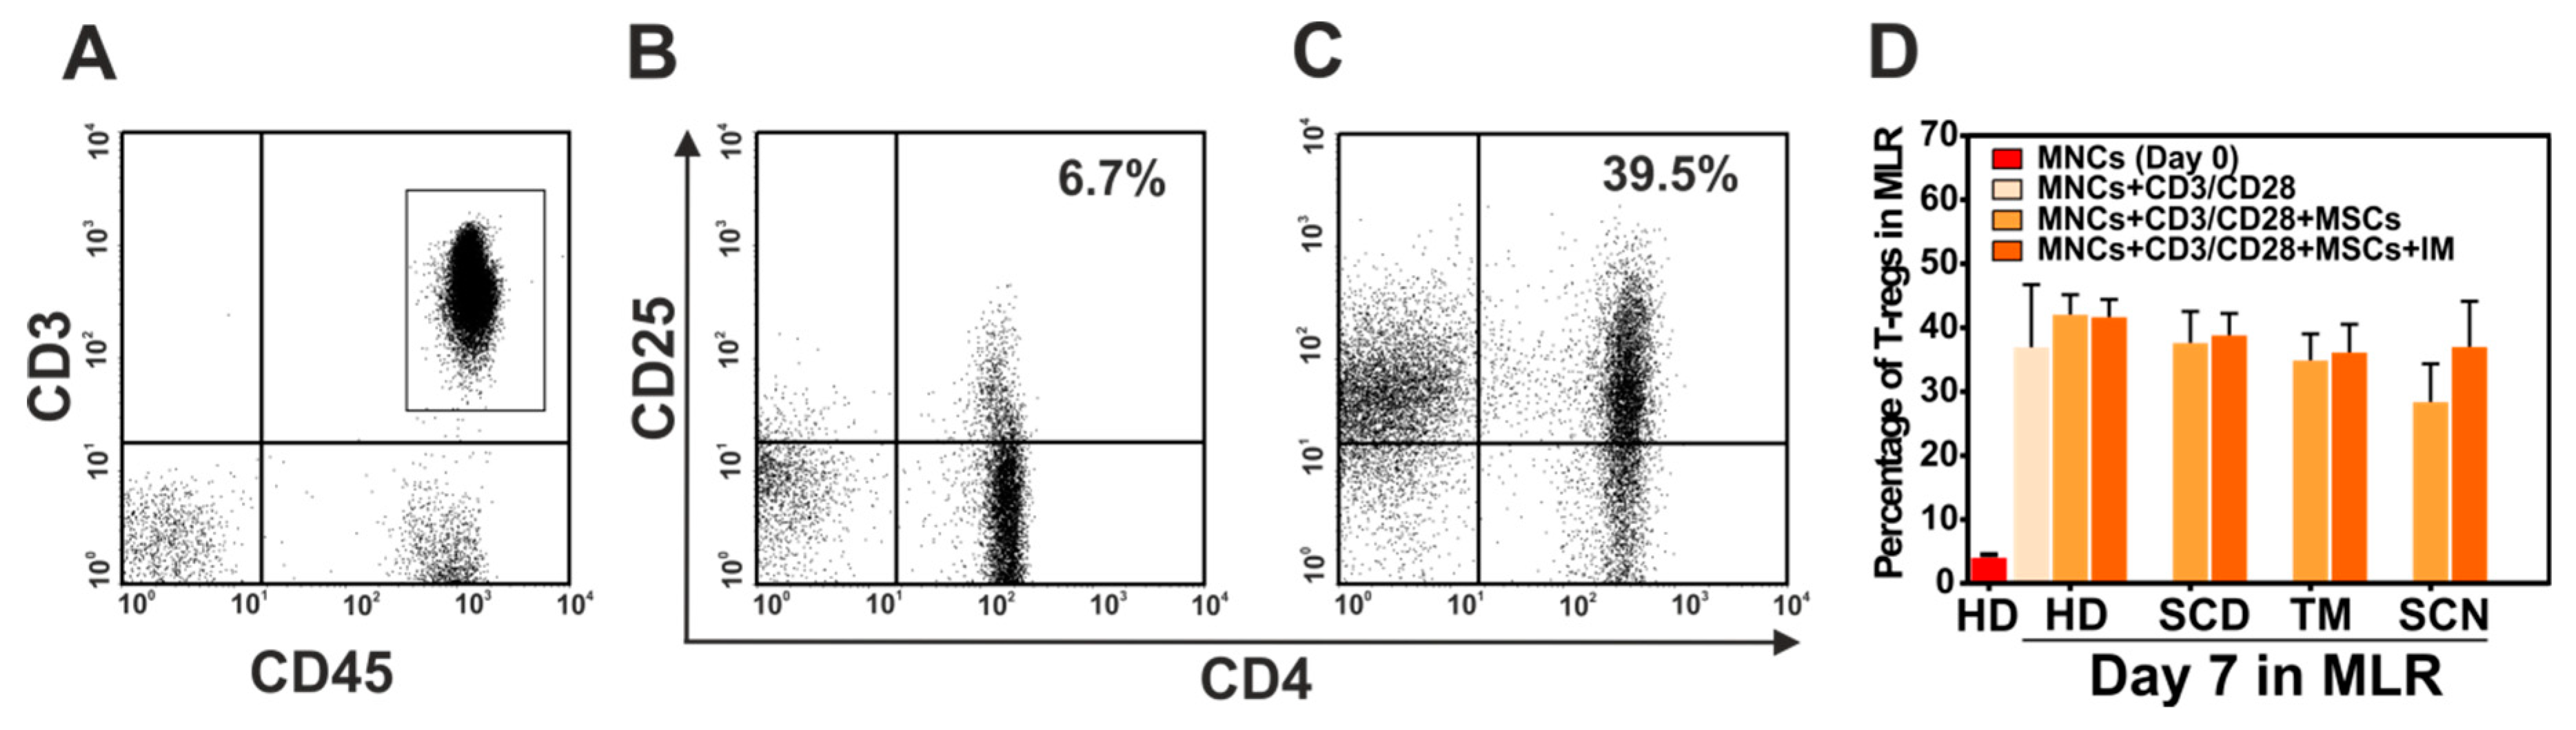

3.6. Immunosuppressive Effect of Mesenchymal Stromal Cells (MSCs) of Patients with Non-Malignant Hematological Diseases (NMHD)